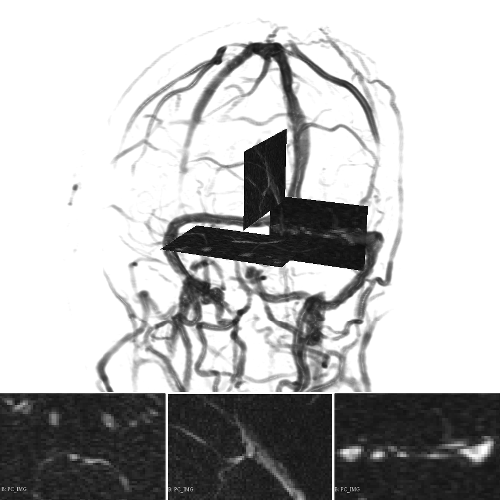

A 3D hand-crafted tortuous and convoluted phantom (HCP) is designed to account for complex vessel patterns, i.e. branching, kissing vessels, scale and shape variations induced by pathologies. Also a set of 20 synthetic vascular trees (SVT) ( voxels) were generated using VascuSynth [10] considering two levels of additional noise (N1: + Shadows: 1 + SaltPepper: ; N2: + Shadows: 1 + SaltPepper: ). Together with the synthetic data, a cerebral Phase Contrast MRI (PC) ( mm), a cerebral Time of Flight MRI (TOF) ( mm) and a carotid CTA ( mm) were used. Vascular network ground-truths (GT) are given in the form of connected raster centerlines for all the synthetic images and for both TOF and CTA.

3.2 Connected Geodesic Paths as Vascular Tree

Representative examples of degraded synthetic images from SVT and the respective GT are shown in fig. 4 together with the connected graphs extracted by VTrails. Analogously, the same set of images are reported for the real images TOF and CTA in fig. 4. Qualitatively, the extracted set of connected geodesic paths shows remarkable matching with the provided GT in all cases. First, we verify the acyclic nature of the graph. We found no cycles, degenerate graphs and unconnected nodes, meaning that the extracted connected geodesic paths represent a connected geodesic tree. Precision and recall are then evaluated for the identified branches. Also, error distances are determined as the connected tree’s binary distance map evaluated at GT. Average errors () precision and recall are reported (meanSD) in table 1. Note that no pruning of any spurious branches is performed in the analysis.

We presented VTrails, a novel connectivity-oriented method for vascular image analysis. The proposed method has the advantage of introducing the SLoGS filterbank, which simultaneously synthesizes a connected vesselness map and the associated tensor field in the same mathematically coherent framework. Interestingly, recent works [17, 9] are exploring Riemannian manifolds of tensors for high-order vascular metrics, however the coherent definition of a tensor field is not trivial for an arbitrary scalar image, as its topology cannot be generally approximated simply by an ellipsoid model [14]. The steerability property of SLoGS stands out as key feature for i. reducing the dimensionality of the kernels parameters in 3D, ii. determining the filterbank’s rotation-invariance and iii. optimizing the 3D filtering complexity in the OLA. Also, the combined rotation- and curvature-invariance of the filtering process results in branch-points that coincide with the locally integrated center of mass of the multiple SLoGS filter responses. This explains the strong response in the CVM at the branch-point in fig. 3. Regarding the acyclic connectivity paradigm employed in VTrails, we experimentally verified that the resulting set of connected geodesic paths forms a tree. The assumption of a vascular tree provides a natural and anatomically valid constraint for 3D vascular images, with few rare exceptions, such as the complete circle of Willis [5]. It is important to note that the proposed algorithm can include extra anatomical constraints to correct for locations where the vascular topology is not acyclic or where noise it too high. Note that despite the optimal formulation of the anisotropic front propagation, a limitation of the greedy acyclic connectivity paradigm is the possibility of miss-connecting branches, potentially disrupting the topology of the vascular network. Overall, promising results have been reported from this early validation, with a fully-automatic extraction configuration. Missing branches occur in correspondence of small vessels, where the effect of degradation is predominant: tiny terminal vessels completely occluded by the corrupting shadows will not automatically produce seeds, hence cannot be recovered under such configuration. Globally, values are comparable to the evaluation tolerance , suggesting that the connected geodesic paths extracted by VTrails lie in the close neighbourhood of the vessels’ centerlines. Moreover, the reported values are comparable regardless the level of degradation. Future developments will address the optimization of the CVM integration strategy in section 2.1 to account for an equalized response over the vascular spatial frequency-bands. Also, the topological analysis of vascular networks on a population of subjects will be investigated in future works to better embed priors in the acyclic connectivity paradigm.